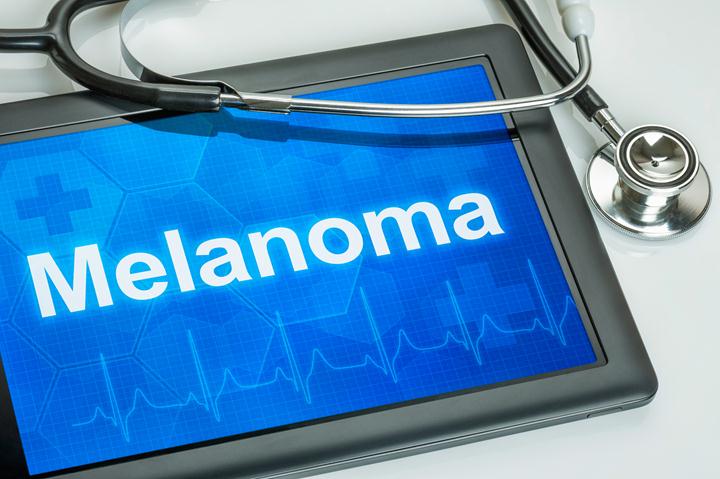

The majority of cases of skin cancer essentially happen on parts of the body that are not exposed to direct sunlight. Besides, many deaths due to skin cancer are actually not more than ten thousand in the complete population of the U.S. To be more exact, there is a...

The most dangerous part of melanoma is its ability, in later stages, to spread (or metastasize) to different parts of the body. Metastatic melanoma, also known as Stage IV melanoma, is the stage where melanoma cells of any kind (mucosal, cutaneous, or visual) have spread through the lymph nodes...

We’ve all heard cancer described as being in a particular stage, with higher numbered stages more serious than lower numbers. But what do these numbers actually mean? Most doctors use a staging system called TNM, which measures tumor formation (T), lymph node involvement (N), and the presence of metastasis. 1....